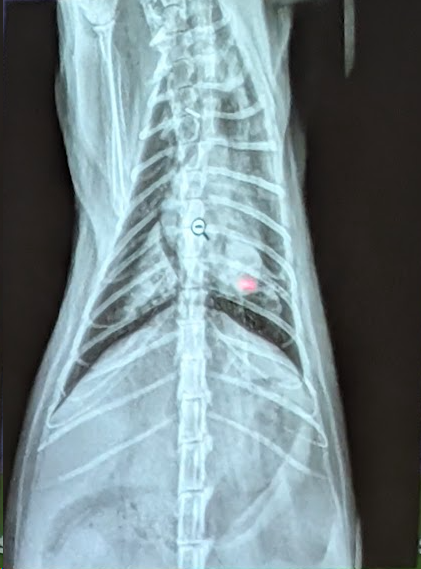

Preguna 7 - Multiple respuesta

- Hay efusion pleural

- Hay Hipertensión pulmonar (dilatación y tortuosidad de las arterias pulmonares, una prominencia del tronco pulmonar y un aumento del tamaño de las cavidades derechas del corazón. En este caso se ve porque si lo comparamos con la 9a costilla vemos que es mucho mas gruesa la arteria de la derecha que la costilla)